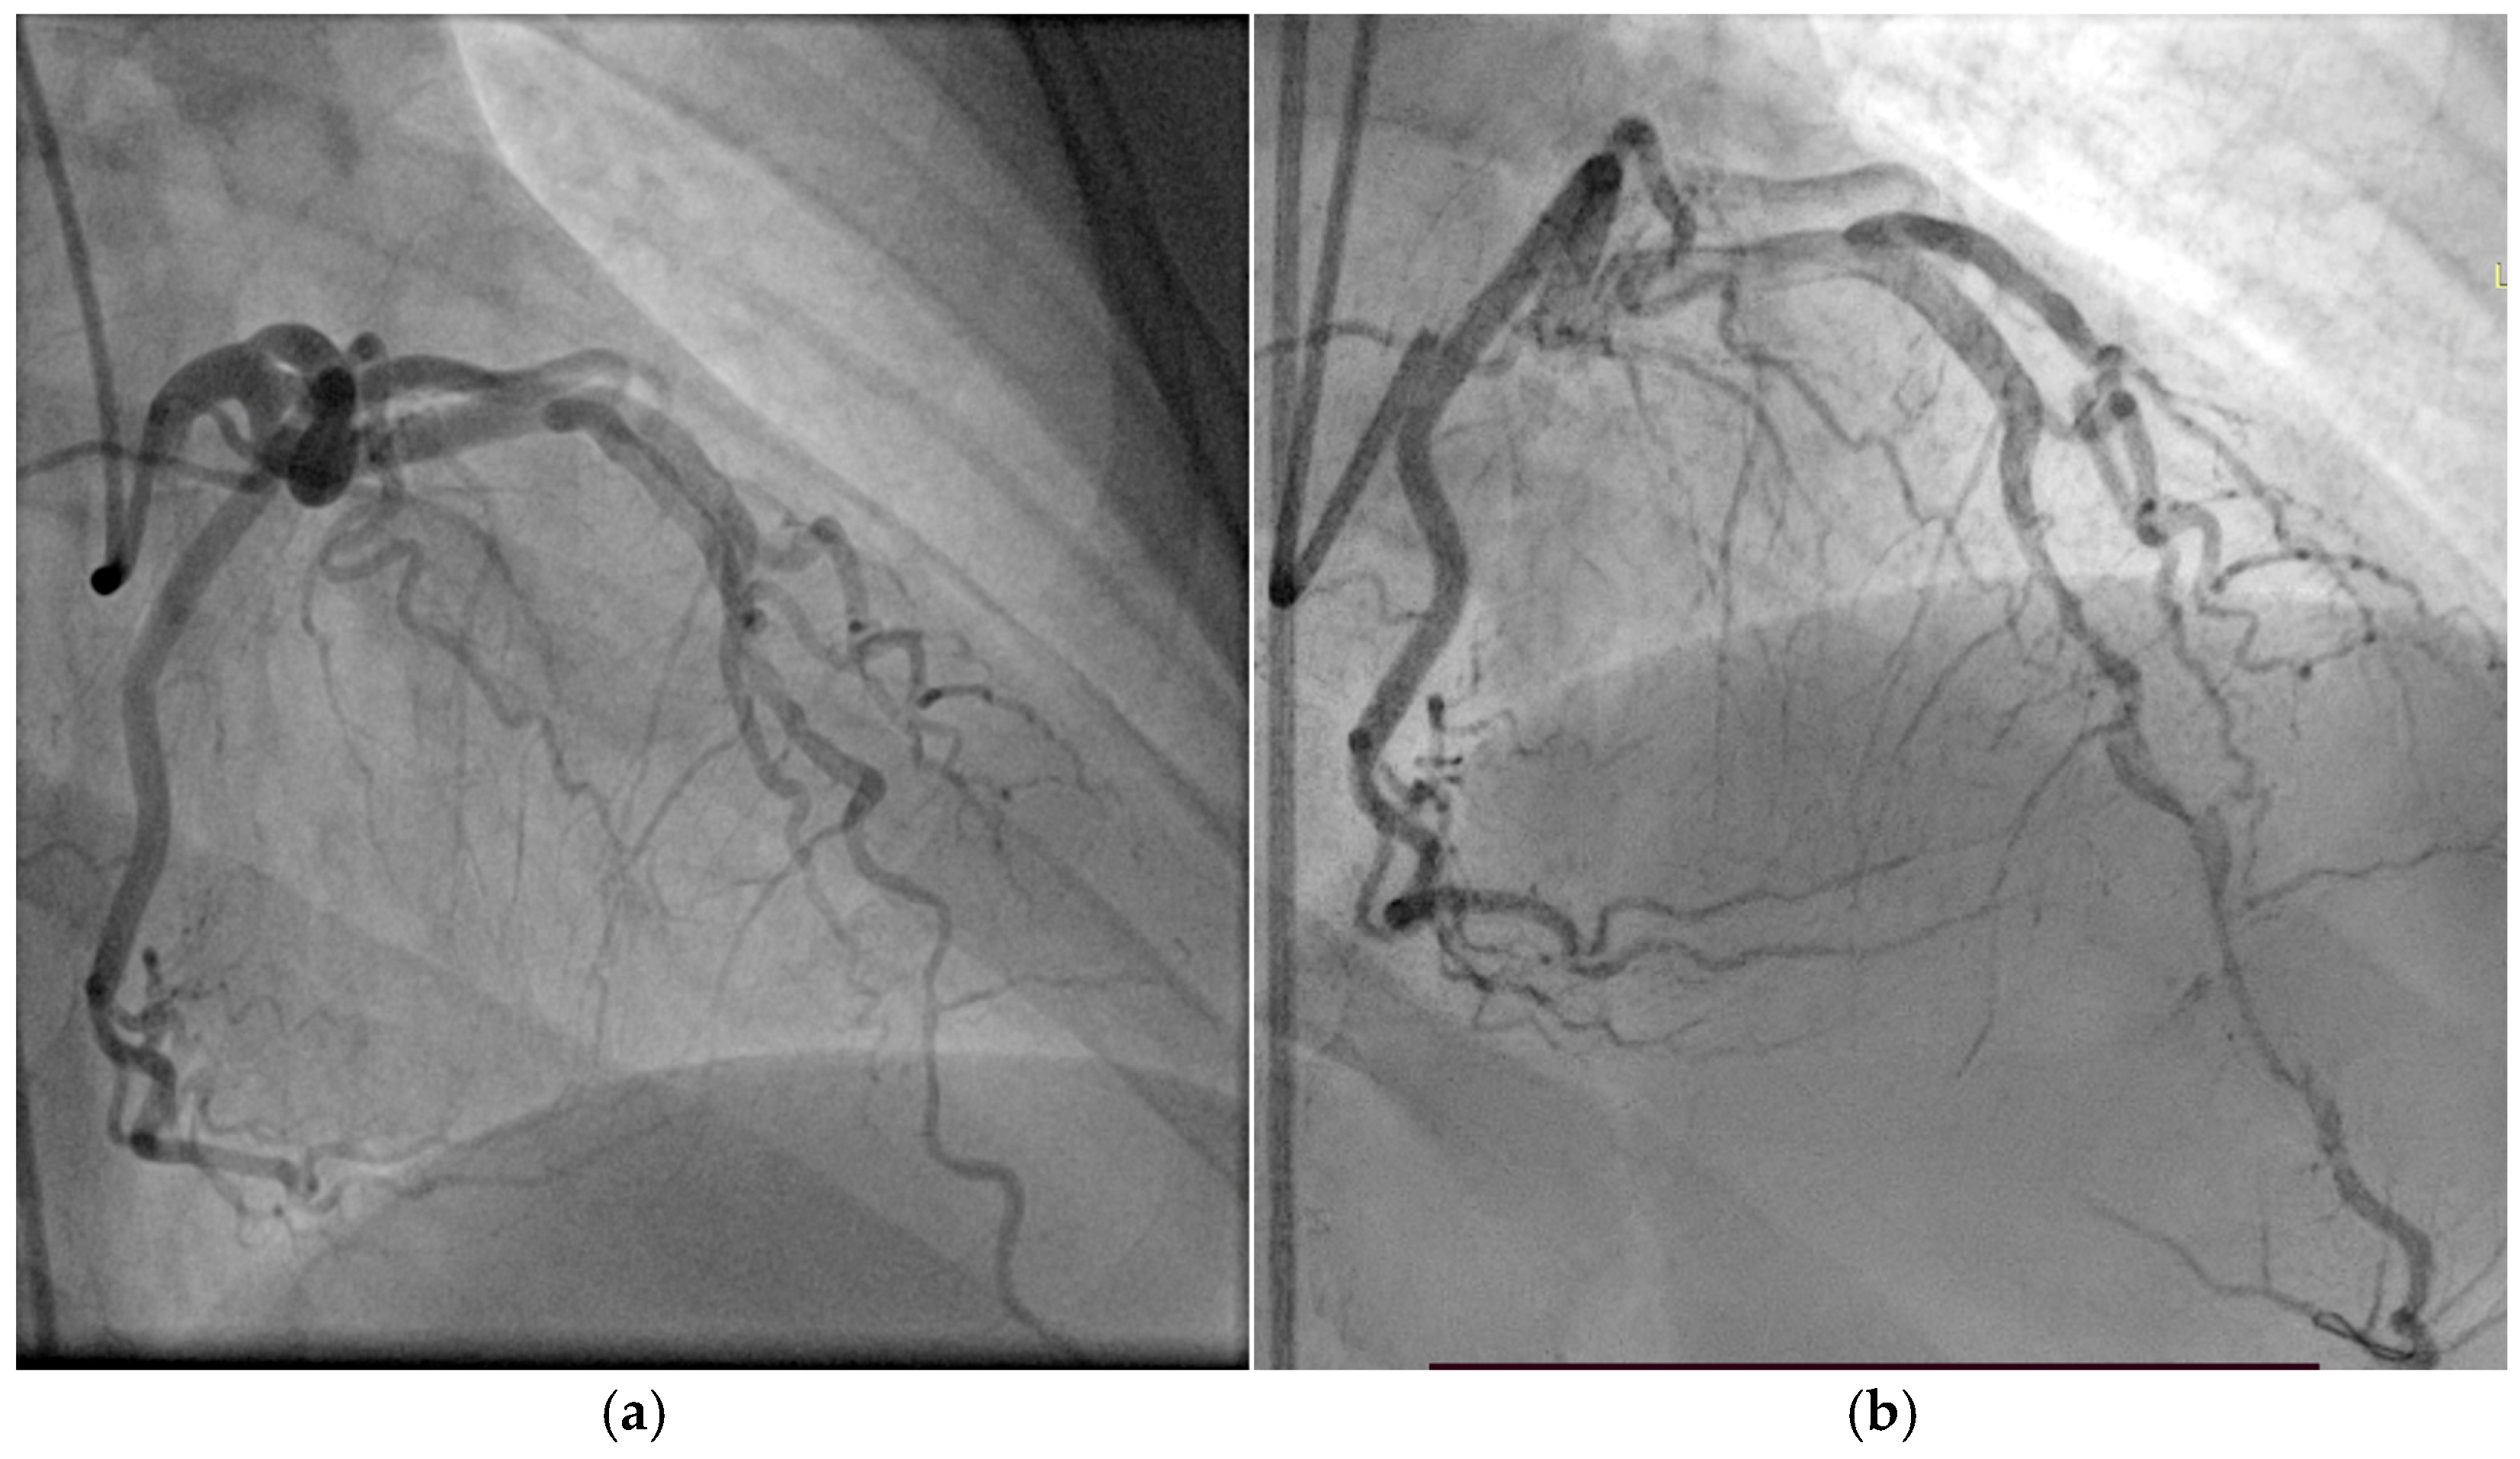

3.1. Case 1

3.2. Case 2

3.3. Case 3

3.4. Case 4